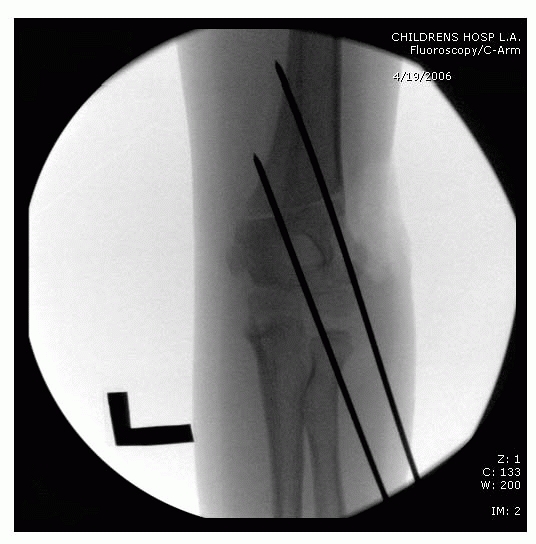

![]() |

FIGURE 14-22

Properly placed divergent lateral entry pins. On the AP view, there should be maximal pin separation at the fracture site, the pins should engage both medial and lateral columns just proximal to the fracture site, and they should engage an adequate amount of bone proximal and distal to the fragments. On the lateral view, pins should incline slightly in the anterior to posterior direction in accordance with normal anatomy. (From Skaggs DL, Cluck MW, Mostofi A, et al. Lateral-entry pin fixation in the management of supracondylar fractures in children. J Bone Joint Surg Am 2004;86(4):702-707, with permission.) |

FIGURE 14-23

Intraoperative fluoroscopy of two lateral entry pins placed for a type II fracture. (Reproduced with permission from Children’s Orthopaedic Center, Los Angeles, CA.) |